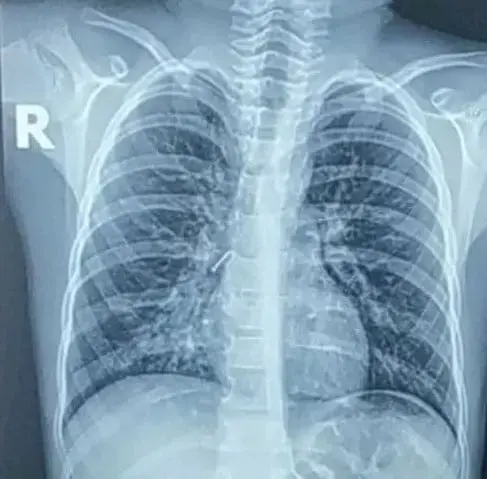

В Днепре врачи изъяли из бронхов 7-летнего ребенка постороннее тело.

По его словам, родители ребенка обратились к семейному врачу с жалобой на постоянный кашель у их ребенка. Впоследствии было выяснено, что ребенок вдохнул канцелярскую кнопку, попавшую ему в правый бронх.

Пациенту пришлось провести ригидную бронхоскопию. При удалении кнопки за ребенком наблюдали реаниматологи и хирурги.